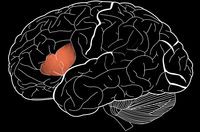

Позднее эта область получила название «центра Брока», и с тех пор считалось, что она играет ключевую роль в понимании и порождении речи.

Но недавно нейробиологи Института мозга Патрика Макговерна при МТИ во главе с Эвелиной Федоренко пришли к выводу, что на самом деле центр Брока состоит из двух четко разграниченных блоков, один из которых отвечает за обработку речи, а другой является частью общемозговой сети, служащей основным центром мыслительных функций.